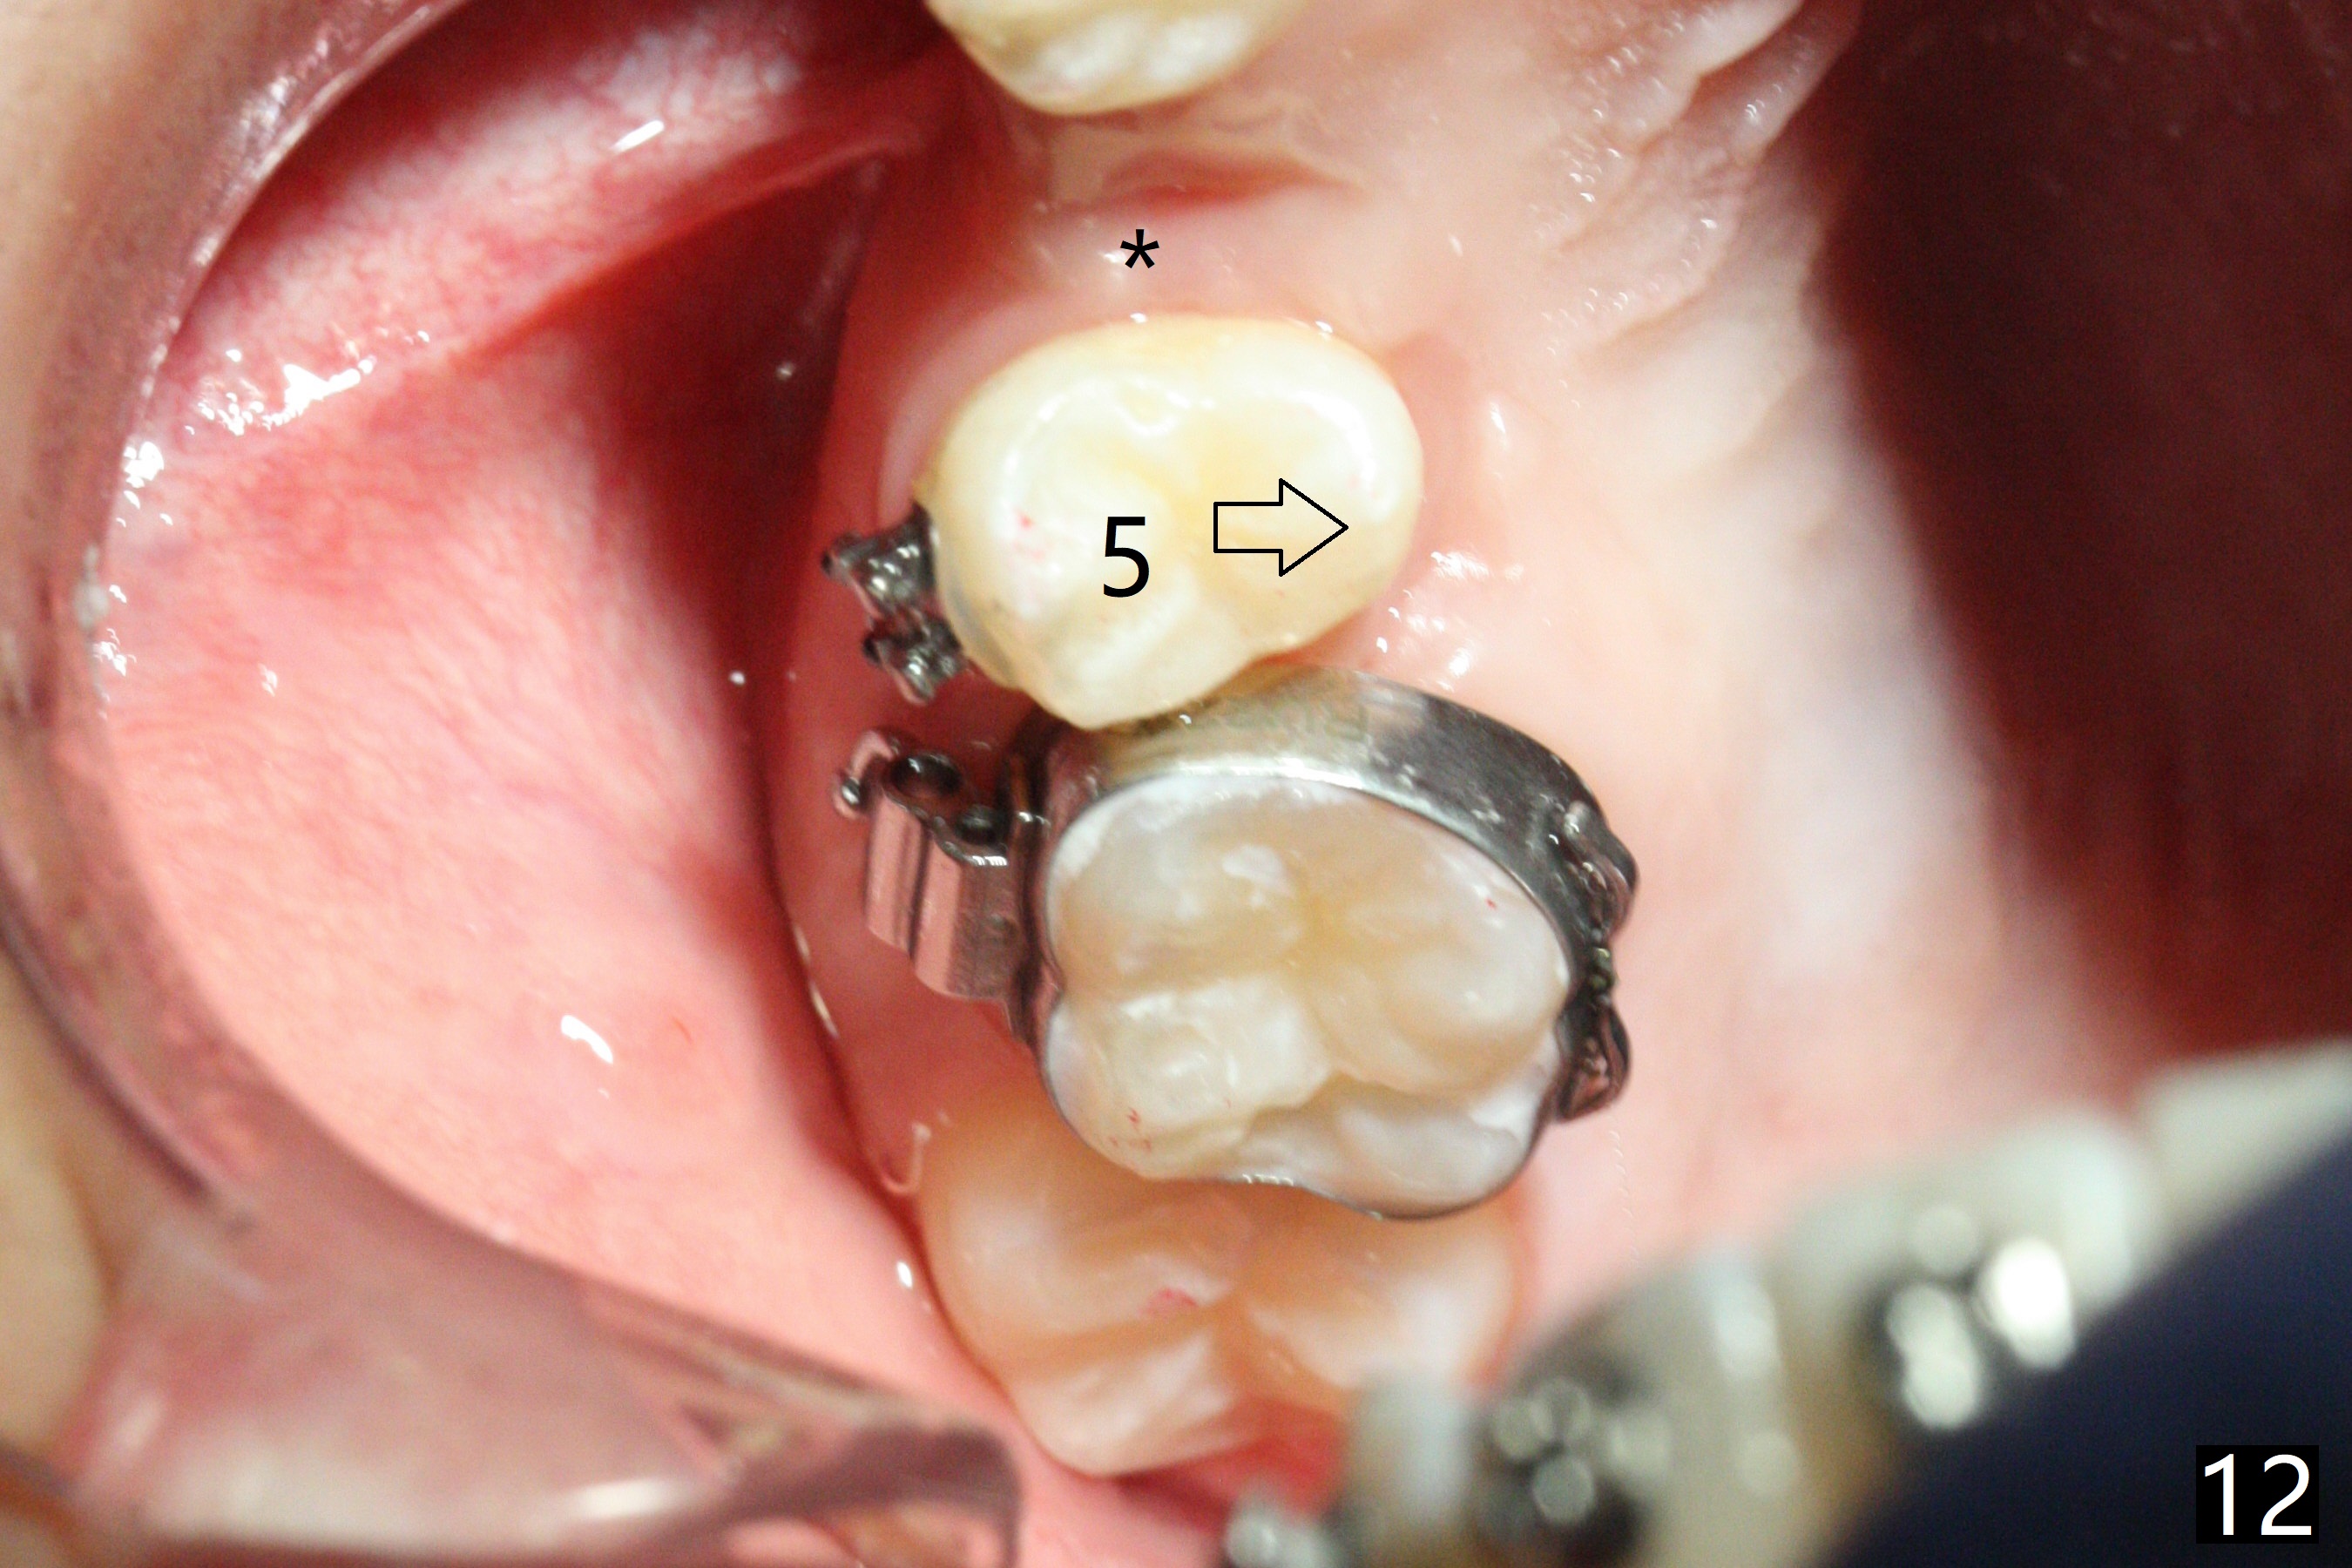

In fact, automatic shifting is striking.  For example, UR5 lingualization (Fig.12 arrow) makes it easy to insert 12 niti wire.  Distalization of the lower bicuspids and canine is more obvious (Fig.13,14 arrows) than the upper counterparts.  Because of incomplete eruption, it is difficult to band L7s; instead brackets are placed (Fig.15-17).  The purpose of LR one is to facilitate LR6 buccalization (Fig.15,16), whereas LL one to correct rotation of itself (Fig.17).